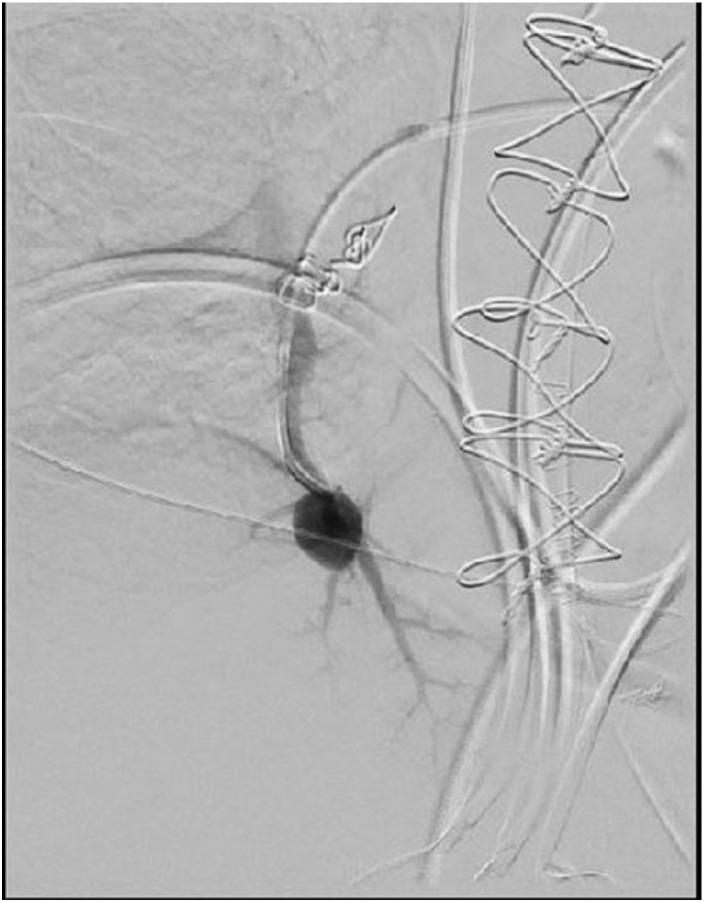

Successful percutaneous embolization of an intraoperative swan ganz catheter-related pulmonary artery injury.

Intraoperative pulmonary artery injury due to Swan Ganz catheterization is a rare but potentially life-threatening injury which demands rapid recognition and treatment. Subsequent pseudoaneurysm formation can occur if not immediately recognized, and percutaneous embolization is a viable option for treatment in most settings. We report a case of a 59-year-old female who underwent coronary artery bypass surgery and suffered an intraoperative Swan Ganz catheter-related injury which led to life threatening hemorrhage with subsequent pulmonary artery pseudoaneurysm formation that was successfully embolized. This case report is pathognomonic for this injury and discusses risk factors, presentation, and treatment options of this rare but serious injury.